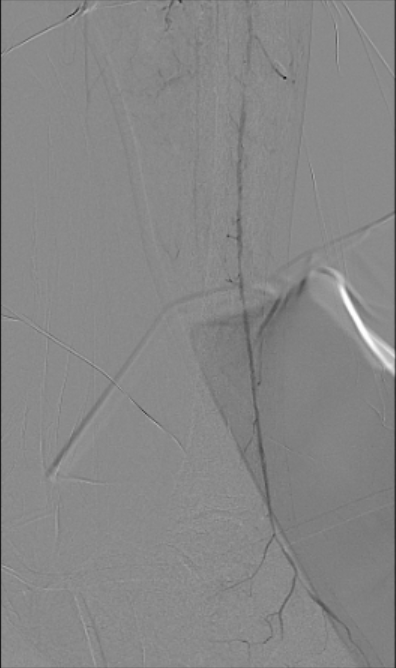

Antegrade puncture was performed, and a microcatheter with a Command 14 guidewire (Abbott Vascular, Santa Clara, CA, USA) was advanced toward the distal SFA but failed to cross because the proximal cap was misidentified due to its blunt and ambiguous appearance. The wire entered aside branch that ran parallel to the true SFA–popliteal course. Given the long chronic total occlusion (CTO) segment and uncertain vessel path, a retrograde approach was pursued to overcome this anatomical ambiguity. Distal ATA access was gained and a CXI Support Catheter (Cook Medical, Bloomington, IN, USA) with a V-18 Guidewire (Boston Scientific, Marlborough, MA, USA) was advanced retrogradely into the popliteal artery but failed to meet the antegrade wire. Another retrograde access from popliteal artery followed a consistent tract. Further attempt from the ATA successfully approached the proximal cap. A 4.0 ¡¿80 mm balloon was advanced retrogradely and inflated at 10 atm. From the antegrade route, the BeBack Crossing Catheter (Bentley InnoMed, Hechingen, Germany) was aimed toward the inflated balloon and successfully punctured the proximal cap, entering the balloon and confirming re-entry. Lesion preparation was completed antegradely, followed by drug-eluting stent deployment in the SFA, drug-coated balloon angioplasty of the popliteal–proximal ATA segment, and plain old balloon angioplasty of the distal ATA to DPA. Final angiography demonstrated excellent in-line flow to the plantar arch.